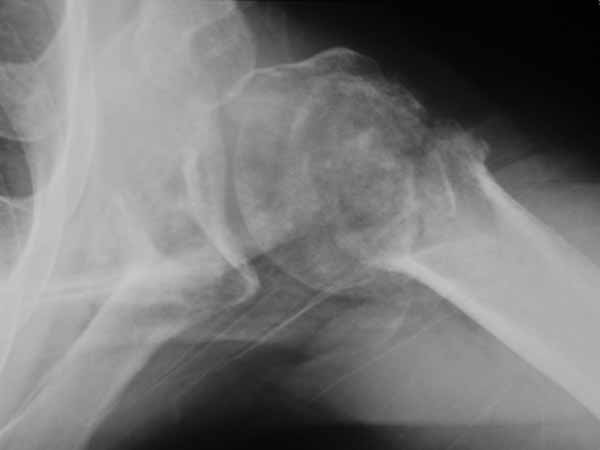

I'd replace it at this point. But if you decide to fix it, i'd use the fixed angled locked screw proximal humerus plate because I think it gives opportunity for many fixed angled points of fixation...more than the single blade for the rod. an example attached (although admittedly not for a nonunion).

I would consider using the Synthes Proximal Humerus Locking Plate through a deltopectoral incision. After disimpacting the head you should be able to get good stabilization even in this very osteoporotic bone with the combination of converging and diverging holes. I would fill in the resulting defect with your bone volume replacement of choice. We still tend to favor autologous bone graft but have also used Norian (the semisolid putty rather than the runny liquid) and other bone graft substitutes. I will try to dig up some intraoperative and clinical photos as well as radiographs.

This was a 23 yo male run over by a boat with multiple propeller injuries. The fixation was carried out after several washouts with good granulation beginning and no evidence of infection. We utilized the one of the lacerations for our modified deltopectoral approach as shown in the first photo. The second photo shows the plate in place, held with a tenaculum forceps. The K-wire fits through the most superior hole in the plate with it's attached template guide. It should skim just superior to the tuberosities across the superior head and is only for positioning the plate. The third photo shows an intraoperative fluoro shot of the plate in position. The K-wire looks to be a little inferior but it may be projection. We have placed a screw through a slotted hole on the shaft to allow proximal and distal correction while maintaining rotational alignment. You can see the drill bit through the tower in one of the proximal locking holes. Sorry these aren't the greatest. I will try to dig up some better shots and some x-rays. I echo the sentiments of others that he is not likely to gain a tremendous amount of motion but we have been surprised on several occasions. From the radiographs you provided it appears that the tuberosities and, therefore, probably the rotator cuff attachments are in the ballpark although you may find it necessary to tack those down with sutures through the plate to restore the integrity of the cuff. Be prepared for the subluxation to persist for quite a while even with stabilization but it will likely improve with therapy if the cuff is attached. I have started these patients on passive, patient controlled ROM on POD #1 with flexion to 90 degrees, abduction to 70-90 degrees, and internal and external rotation to 90 degrees and neutral respectively. I'm encouraged that some recent articles have looked at comparisons between ORIF and hemiarthroplasty for Neer IIIs and IV and shown very similar results. I will send the references as soon as I am able to locate the article in my mountain of journal club articles waiting to be filed. We don't have a large series yet because the plates are relatively new (I think we were a test market) but in the dozen or so we have done we have not had any nonunions and all have had significant improvement in pain. Good luck. Warmest regards,